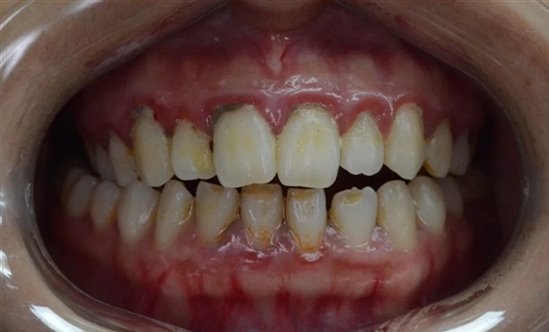

1.牙龈红肿,易出血,可发生于个别牙或全口牙龈,前牙区较重;

2.个别患者出现妊娠瘤,发生于单个龈乳头,可有蒂或无蒂,一般不痛,易出血,严重者妨碍进食